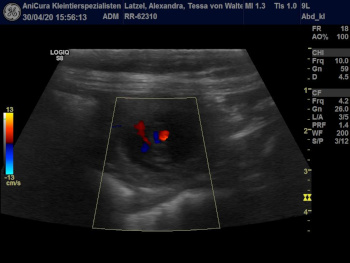

Aennchen und Tessa sind Schwanger! Hier sind die Ultraschallbilder !!! |

| Die Ultraschallbilder von Aennchen von Waltenweiler!!! |